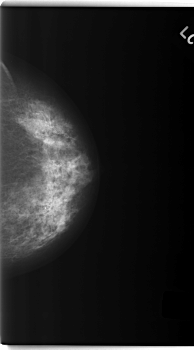

C_0232_1.LEFT_CC

LEFT_CC LINES 5936 PIXELS_PER_LINE 3296 BITS_PER_PIXEL 12 RESOLUTION 50 NON_OVERLAY